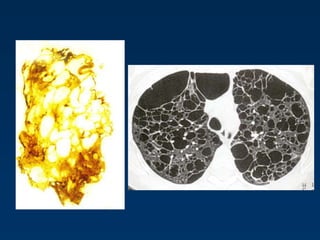

Lymphangioleiomyomatosis (LAM)

HRCT Morphology

Thin-walled cysts (2mm - 5cm)

Uniform in size / rarely confluent

Homogeneous distribution

Chylous pleural effusion

Lymphadenopathy

in young women

Tuberous Sclerosis (young man)